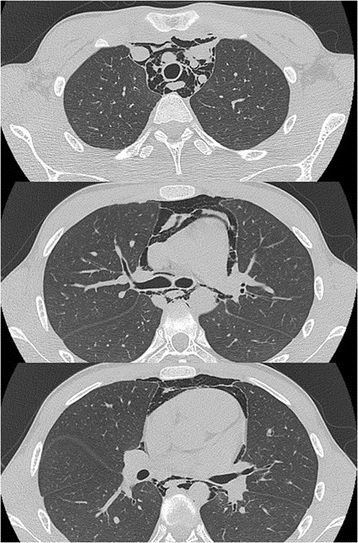

Findings: A 12-year-old boy presented with sustained chest pain and dyspnea after diving into a swimming pool and was transferred to our emergency department. A chest examination noted a crunching and rasping sound at the precordium, synchronous with the heartbeat. Chest radiography showed lucent streaks and the mediastinal pleura at the left cardiac outline. Additionally, computed tomography showed massive pneumomediastinum surrounding the heart. Thus, he was diagnosed with spontaneous pneumomediastinum.